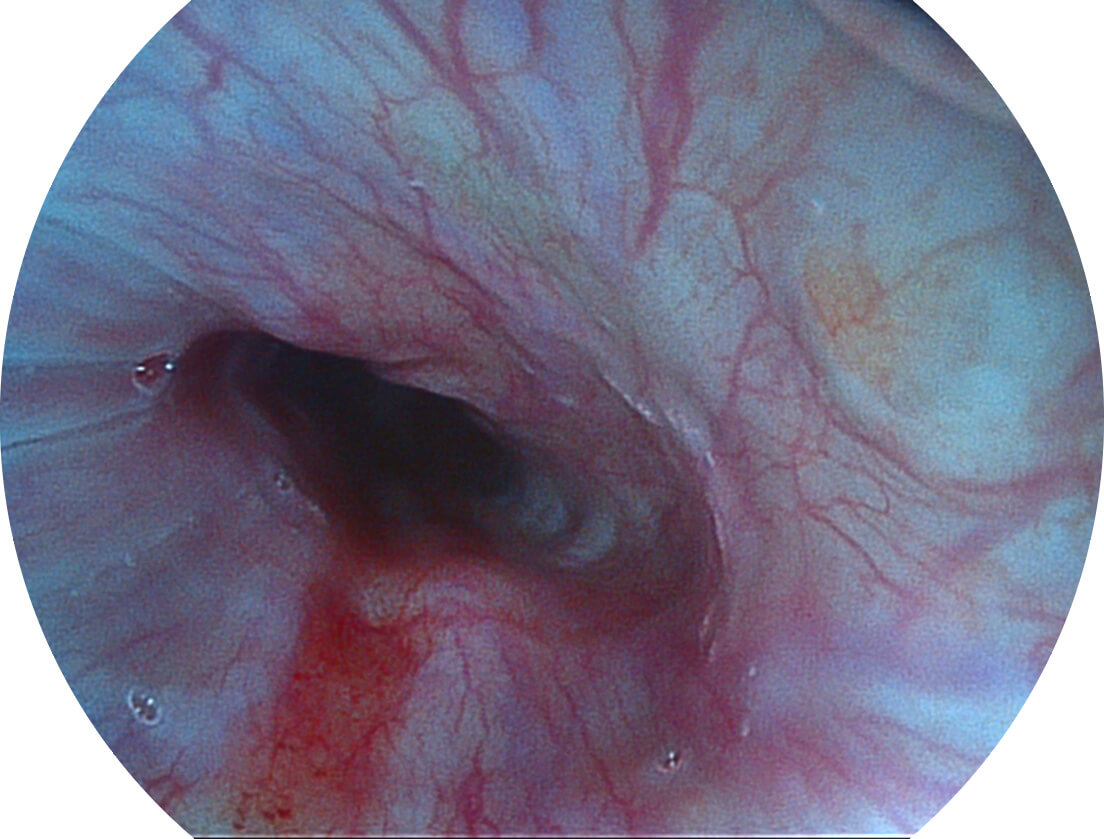

Versatile Intelligent Staining Technology, VIST

强调浅层黏膜结构的同时,保证照明亮度和提升浅层微血管与中层血管颜色对比度,病变边界更清晰。

VIST图像

采用光路合束技术,光谱自由度高,实现了更丰富的照明模式,染色模式SFI及VIST,从远景到近景,助力消化道早期疾病诊断。